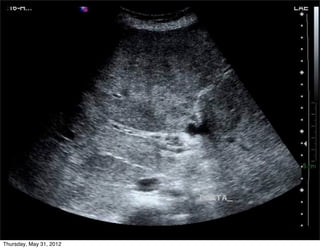

Diagnóstico: ????

T12-L1